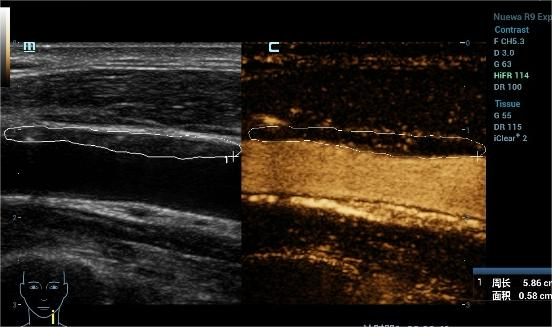

超声造影是在常规超声检查的基础上,通过静脉注射超声造影剂,增强对比作用,无创性评价斑块的稳定性及急性脑血管疾病的发生风险,弥补了常规超声的不足,是一种诊断颈动脉易损斑块的安全、有效、无创的检查方法。

05颈动脉的超声造影报告怎么看?

我们把颈动脉斑块造影分做4级:I~IV级依此显示新生血管从无到有,逐步增多。其中I~II级为稳定斑块,II~IV级为易损斑块。我们可以借助超声造影清晰地显示斑块的表面溃疡,整体形态等结构; 还能清晰显示动脉管腔狭窄的位置以及是否合并闭塞,指导临床进一步干预及评估干预效果。